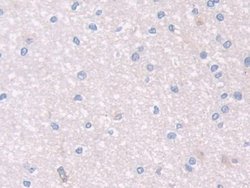

PON2 Polyclonal Antibody for Western Blot, IHC (P)

This gene encodes a member of the paraoxonase gene family, which includes three known members located adjacent to each other on the long arm of chromosome 7. The encoded protein is ubiquitously expressed in human tissues, membrane-bound, and may act as a cellular antioxidant, protecting cells from oxidative stress. Hydrolytic activity against acylhomoserine lactones, important bacterial quorum-sensing mediators, suggests the encoded protein may also play a role in defense responses to pathogenic bacteria. Mutations in this gene may be associated with vascular disease and a number of quantitative phenotypes related to diabetes. Alternatively spliced transcript variants encoding different isoforms have been described.Specifications

| Immunohistochemistry (Paraffin), Western Blot | |